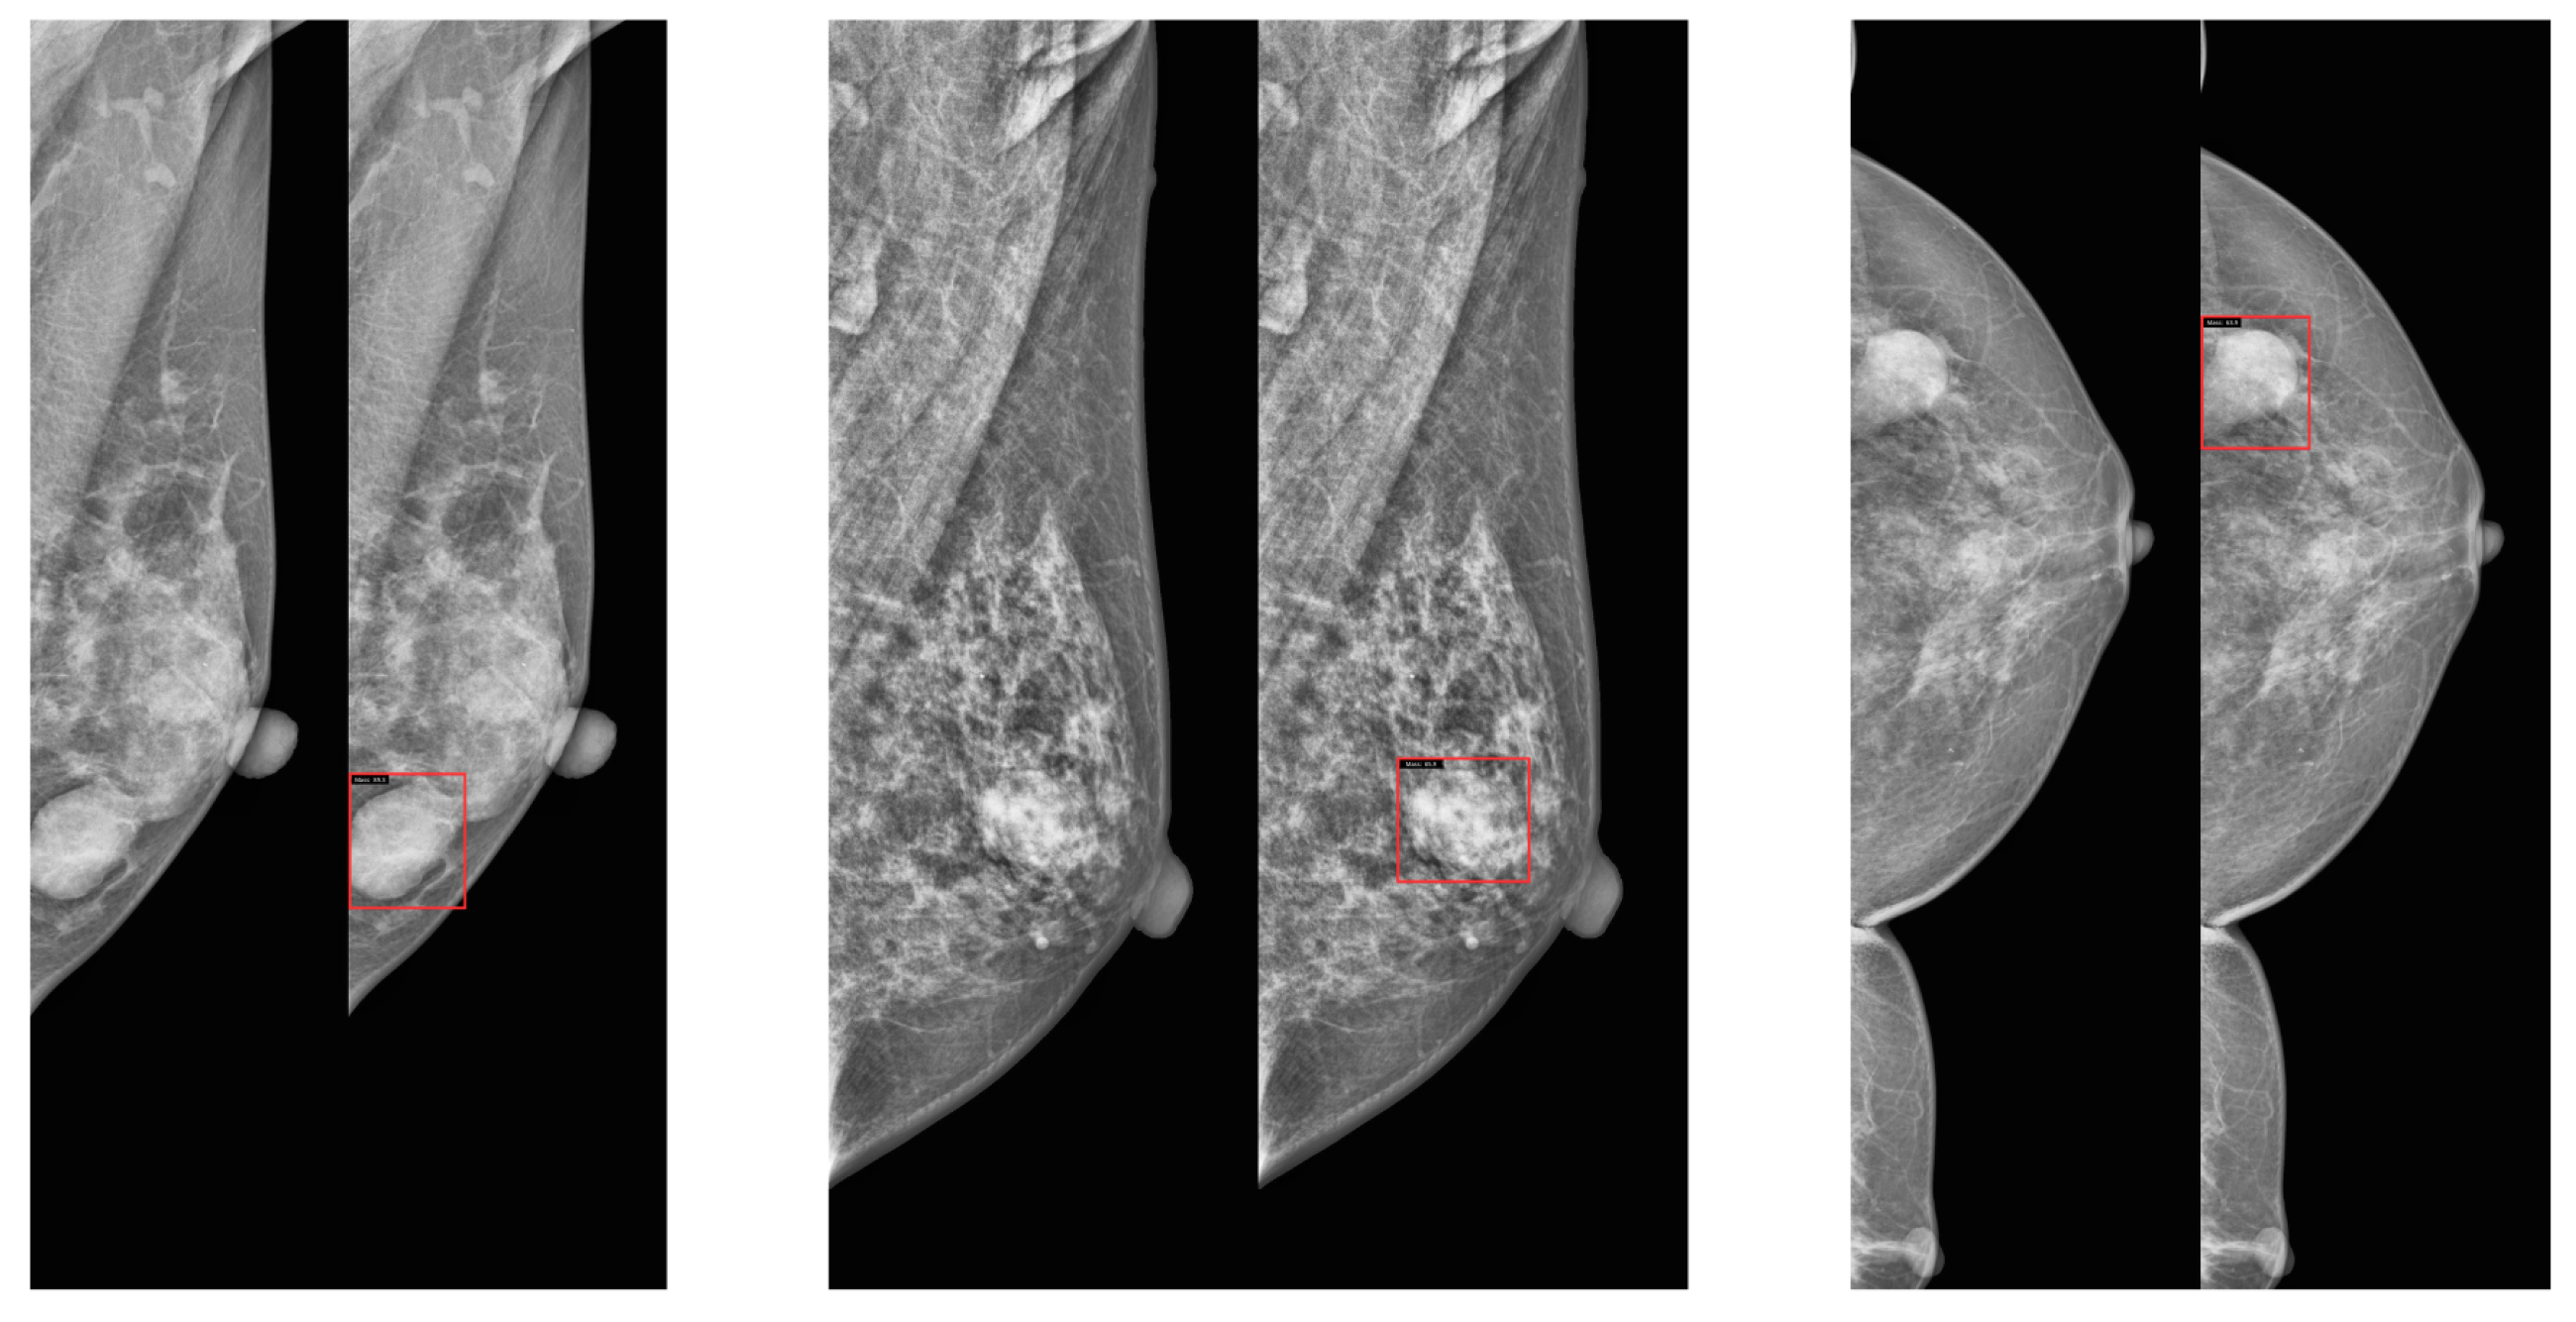

Visualization of Model Performance